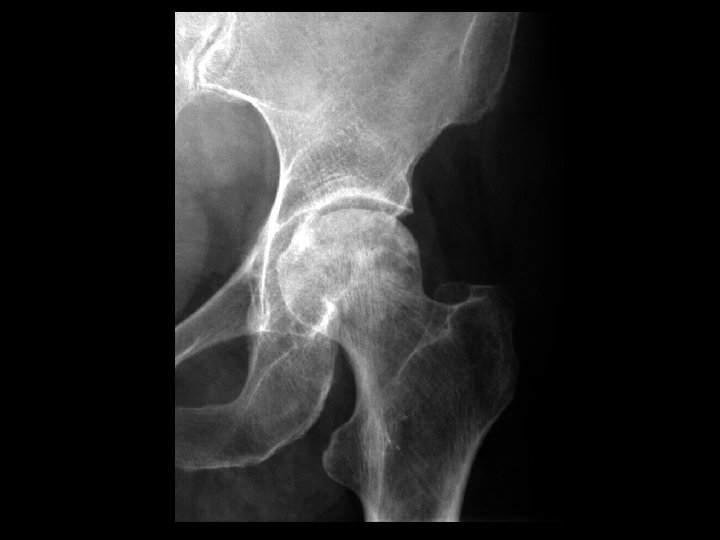

Femoral Head AVN with collapse • Findings: – Mixed sclerotic and lytic appearance of the femoral head – 2 mm collapse of the superior articular surface – Joint space still preserved • ddx: – NONE! – This is an Aunt Minnie!